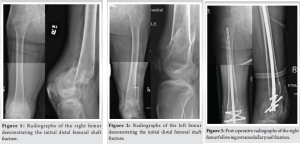

An active, independent 45-year-old male with a history of unresolved T2 paraplegia presented to the emergency department following a motor vehicle accident in which he sustained bilateral closed distal femoral shaft fractures (Fig. 1 and 2) and a left pilon fracture. Surgical intervention was recommended to maintain his current activity levels and to avoid prolonged immobilization. He underwent bilateral femoral retrograde intramedullary nail fixation (Fig. 3 and 4) and left ankle external fixation. The patient was discharged 3 days postoperatively to home with home health assistance; however, he returned the following day due to the inability to perform activities of daily living independently and was ultimately discharged to an acute care rehabilitation facility. He was successfully discharged home from the acute care rehabilitation facility and underwent outpatient removal of the left ankle external fixator and tibiotalocalcaneal (TTC) arthrodesis with a TTC nail 1 month after the initial surgery.